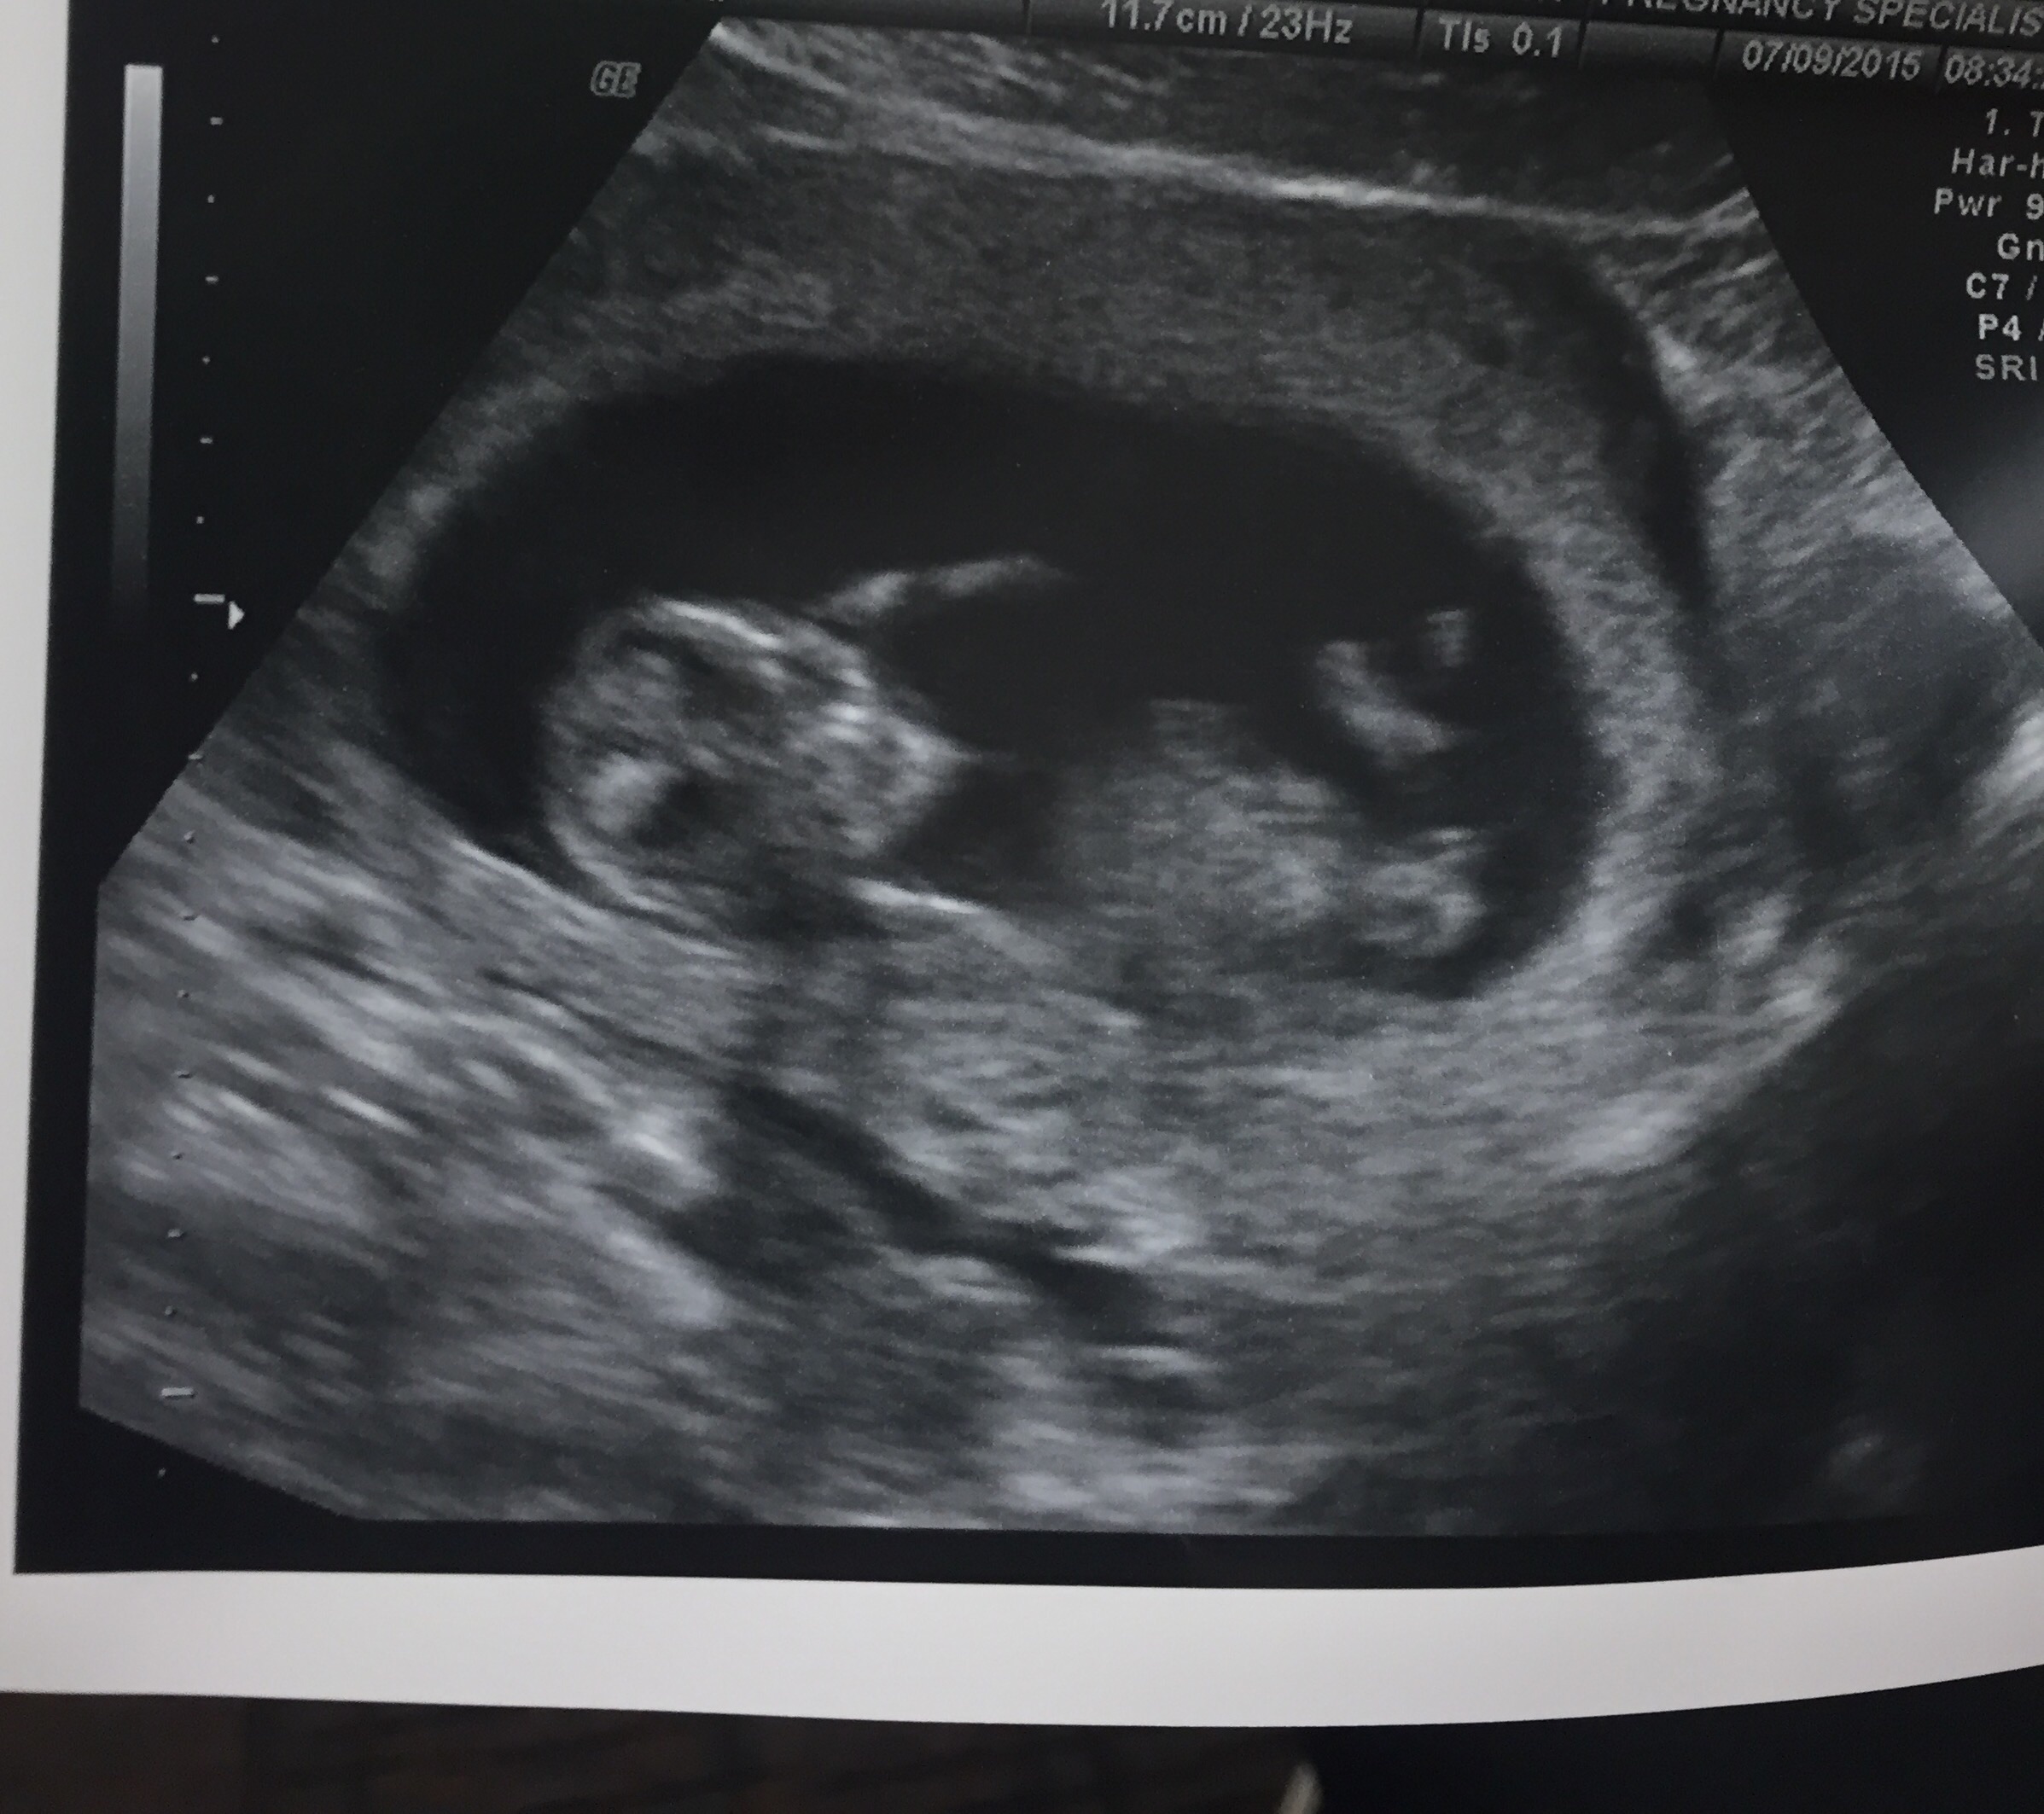

I had my first ultrasound on July 7th. It was great. My little peanut is such a wiggle worm. He/she would not sit still long enough to get good pictures. But they still managed. I was 13 weeks and 3 days, but now measuring at 14 weeks with a heartbeat of 161. Still don't know the gender, I can't wait to find out though. For some reason it won't let me post a picture.